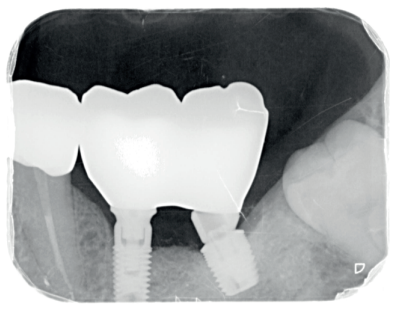

La fluorosis dental es una condición irreversible originada durante el desarrollo dental que genera pigmentaciones intrínsecas, alteraciones en el esmalte manifestadas a manera de manchas blancas, amarillas o marrones, que perjudican la estética y repercuten en el desenvolvimiento social. El presente reporte de caso clínico describe la combinación de los procedimientos de microabrasión y blanqueamiento dental, como alternativas en la eliminación de pigmentaciones dentales. Después del diagnóstico de la patología, verificación de ausencia de lesiones pulpares y caries, una explicación minuciosa a la paciente y obtención del consentimiento informado, se realizó limpieza de las superficies dentales y, bajo aislamiento absoluto, se procedió a realizar la técnica de microabrasión mediante ácido clorhídrico al 6,6% siguiendo las instrucciones del fabricante. Concluido el procedimiento y, observando que era posible mejorar aún más la estética, se decidió ejecutar el procedimiento de blanqueamiento dental, a base de peróxido de hidrógeno al 40% en el consultorio, seguido por peróxido de carbamida al 10% aplicado en el domicilio. Al finalizar el tratamiento se observó uniformidad en el color dental, conjugados con una evidente mejora en la calidad de vida y relación social de la paciente.